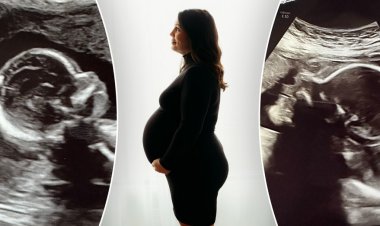

Alabamalı iki rahmi olan kadın, her rahminde bir tane olmak...

32 yaşındaki Kelsey Hatcher'ın nadir görülen çift rahim durumu var. Alabamalı anne şu anda her rahimde bir tane olmak üzere ikizlere...

Nadir görülen çift rahmi olan Alabamalı kadın 'mucize'...

32 yaşındaki Kelsey Hatcher'ın iki farklı rahimden doğacak ikizlerini doğurmasına sadece birkaç gün kaldı. Alabamalı anne, nadir görülen...

Alabamalı çift rahimli kadının 'mucize ikizleri' dünyaya...

32 yaşındaki Kelsey Hatcher, "50 milyonda bir" hamileliğiyle manşetlere çıktıktan sonra ikiz kız çocukları dünyaya getirdi. Alabama...